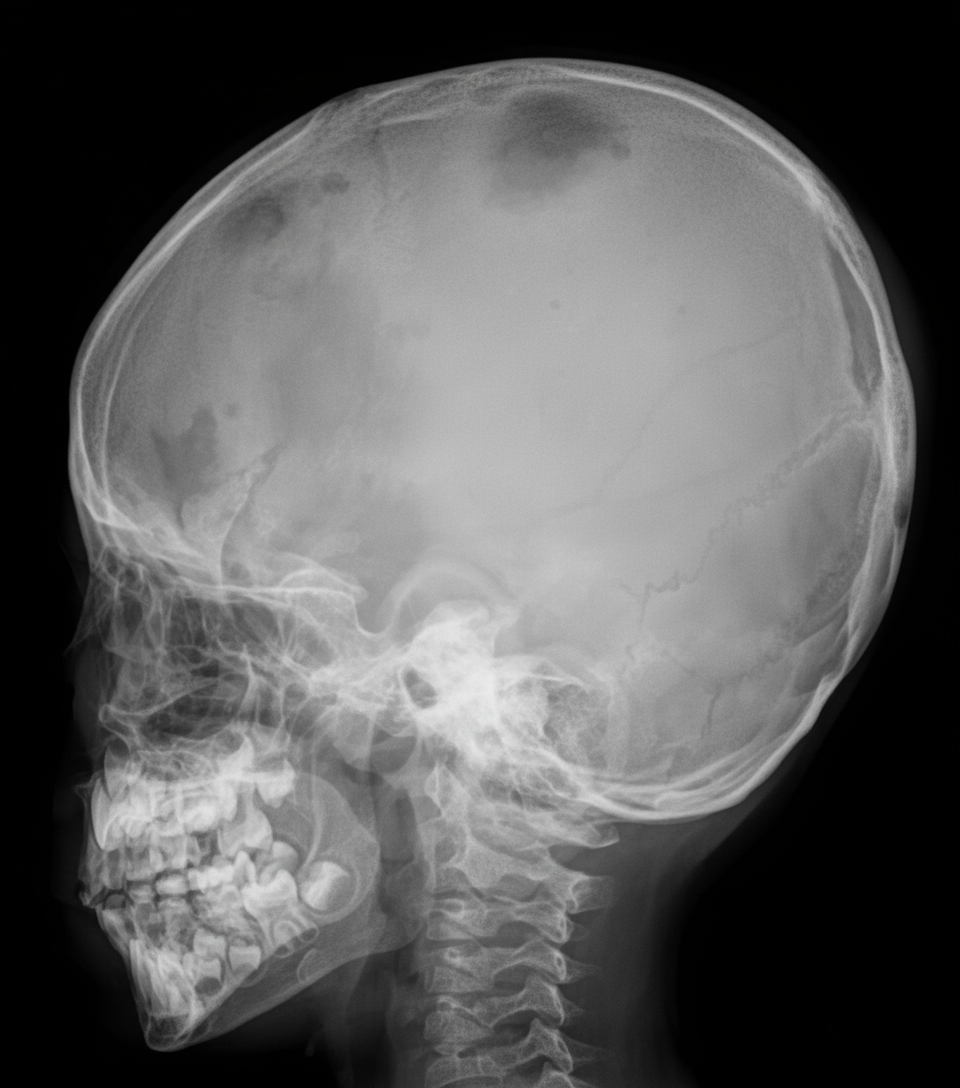

An infant presents with bony pain and dermatitis on the scalp. Skull X-ray and electron microscopy of a biopsy from a lesion are provided. What is the most probable diagnosis?

Explanation: ***Langerhans cell histiocytosis*** - **Classic triad** in infants includes **bony lytic lesions**, **scalp dermatitis**, and **diabetes insipidus**, with skull X-ray showing characteristic **punched-out lesions**. - Electron microscopy reveals pathognomonic **Birbeck granules** (tennis racket-shaped organelles) within Langerhans cells, confirming the diagnosis. *Multiple myeloma* - Primarily affects **adults over 60 years**, making it extremely rare in infants and children. - Presents with **hypercalcemia**, **renal dysfunction**, and **anemia** rather than scalp dermatitis. *Thalassemia* - Characterized by **hemolytic anemia**, **splenomegaly**, and **growth retardation** due to defective hemoglobin synthesis. - Does not cause **lytic bone lesions** or **dermatitis**; instead shows **extramedullary hematopoiesis**. *Acute myeloid leukemia* - Presents with **pancytopenia**, **bleeding**, and **infections** due to bone marrow infiltration by malignant cells. - Does not typically cause **punched-out skull lesions** or **scalp dermatitis** seen in this case.